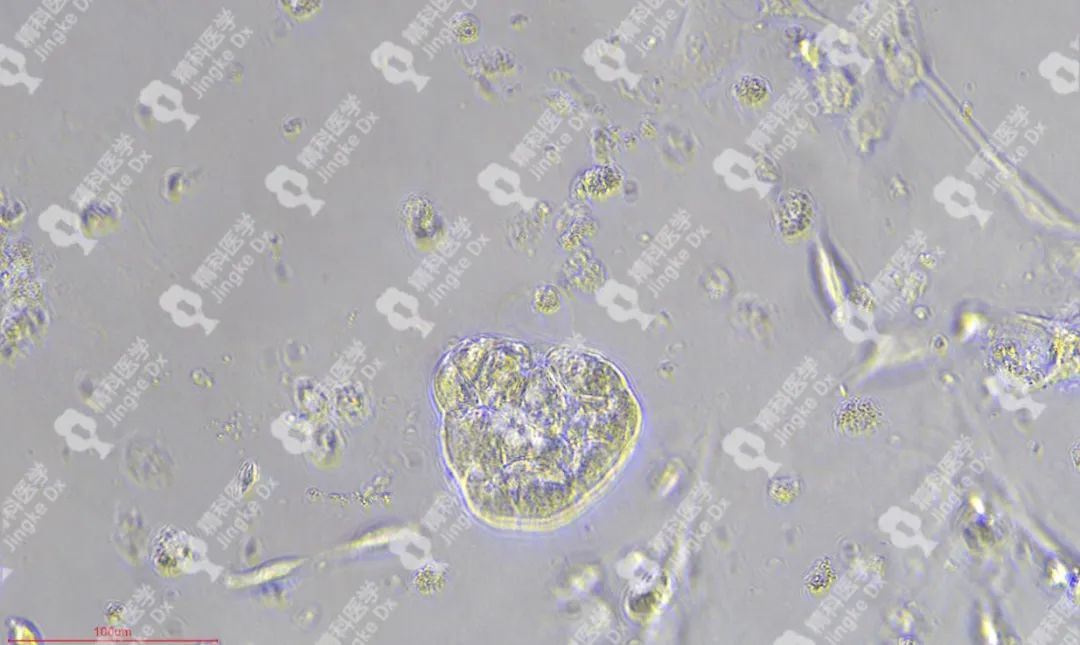

精科類(lèi)器官培養(yǎng)相關(guān)服務(wù) 精科醫(yī)學(xué)作為類(lèi)器官技術(shù)轉(zhuǎn)化先行者致力于推動(dòng)類(lèi)器官技術(shù)的轉(zhuǎn)化與應(yīng)用,對(duì)基于類(lèi)器官培養(yǎng)擁有成熟的技術(shù)與經(jīng)驗(yàn)。精科類(lèi)器官團(tuán)隊(duì)技術(shù)深耕十余年,擁有國(guó)內(nèi)頂級(jí)的類(lèi)器官團(tuán)隊(duì),超微量建模技術(shù)成功率高達(dá)95%以上,有成功建模30+種腫瘤的經(jīng)驗(yàn)(包括上述子宮內(nèi)膜癌、宮頸癌和卵巢癌)。可以提供包含類(lèi)器官建模與保存(建模、凍存、傳代)、類(lèi)器官檢測(cè)(類(lèi)器官H&E染色、免疫組化、藥物敏感度篩選)等多種類(lèi)器官相關(guān)服務(wù)。檢測(cè)服務(wù)最快可在十個(gè)工作日內(nèi)完成,更好為患者爭(zhēng)取治療時(shí)間。 ★ PIC.01 精科卵巢癌類(lèi)器官圖像 ★ PIC.02 精科宮頸癌類(lèi)器官圖像 ★ PIC.03 精科子宮內(nèi)膜癌類(lèi)器官圖像